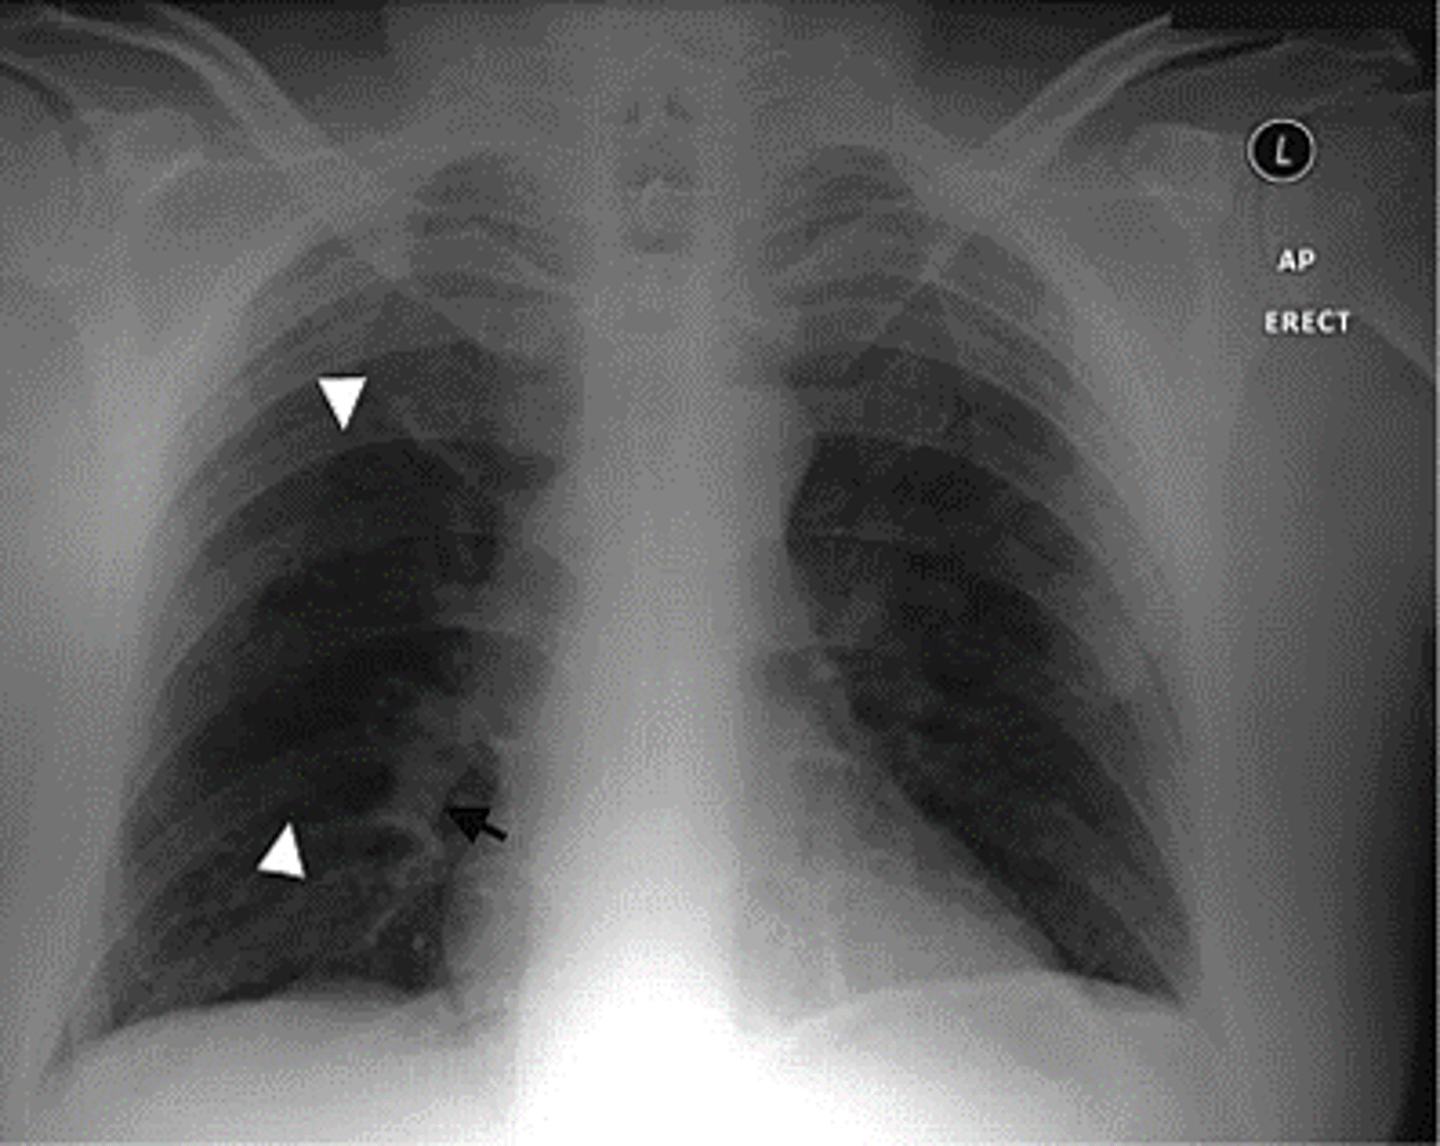

PE (hamptoms hump and westermark sign)

most often normal, but when not it looks like this

lack of vascular markings downstream of clot

westermark sign

pleural based opacities with convex medial margins, wedge-shaped, suggest infarct

hamptom hump